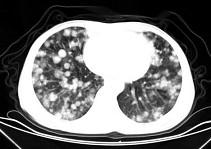

问题 男,42岁,肝区痛一月余,最近二周咯血丝痰,胸部CT如图,最可能的诊断为 ( )

选项 A、肺转移瘤 B、韦格肉芽肿 C、过敏性肺炎 D、结节病 E、葡萄球菌肺炎

答案 A